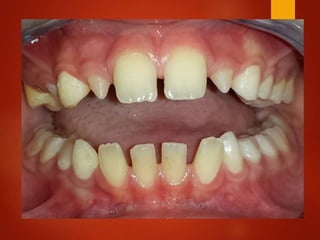

El documento es un registro médico odontológico que muestra las fechas de las visitas de un paciente al centro de salud El Raval, incluyendo exámenes y tratamientos realizados como la extracción de cálculos salivales en abril y mayo de 2012.